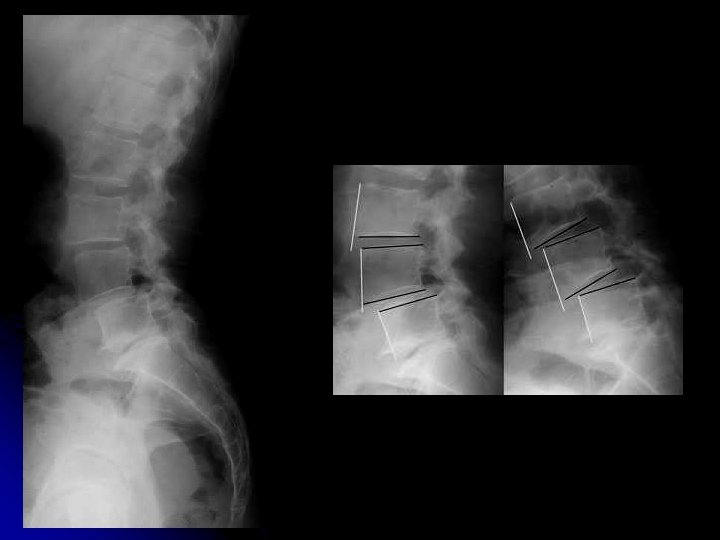

l Autres incidences: l Cliché centré sur L 5 -S 1 l Obliques l Dynamiques

King et Morgan Posner Dvorak